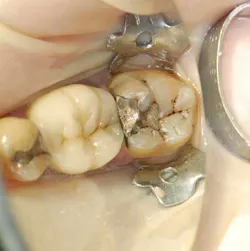

A 55-year-old male patient presented with a chief complaint of occasional hot and cold sensitivity involving his lower molar. Upon clinical examination, it was determined he had a failing amalgam and undermined mesial buccal cusp involving his second molar (Fig. 1). As per the Morgan and Presley’s prewedge protocol, a medium wedge was placed between the molars to initiate separation and protect the papilla. Upon removal of the old restoration and decay, it was decided to restore this tooth with a posterior composite material using the ABC Wedge. With a little imagination, this wedge looks like an elephant’s head and its parts will be described as such. The ears were designed to support the sectional band in three dimensions (3-D) and prevent the sectional rings from crushing in the matrix band (Fig. 2). The elephant’s trunk is analogous to the anatomic wedge. Two wedges were used from the buccal and lingual surfaces, and the curved trunks slide past each other to seal off the gingival floor (Fig. 3). A central groove is located on the back between the ears to line up the sectional separating ring and directs the pressure interproximally for maximum separation. The tooth was then easily restored in incremental layers, trimmed back, and the bite was adjusted (Fig. 4).